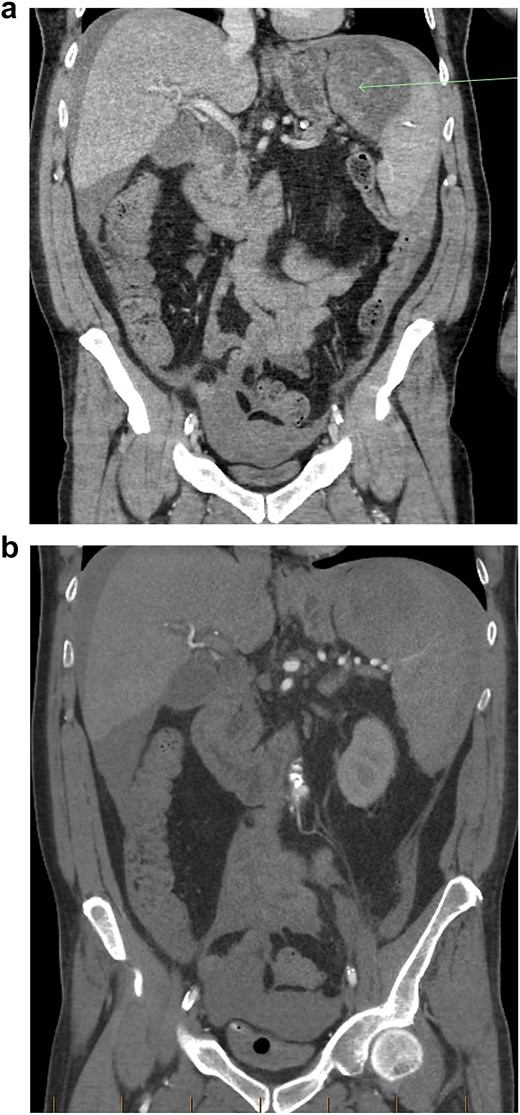

(a, b) Intraoperative specimen showing a large capsular tear with a large haematoma.

The patient responded well to intravenous (IV) fluid resuscitation. Urgent surgical and intensive care reviews were attended. It was determined that the cause for the patient’s presentation was spontaneous splenic rupture, likely secondary to occult haematological malignancy, complicated by tumour lysis syndrome, as well as anuric acute renal failure. A subsequent CT-angiogram was urgently obtained, which did not reveal and active splenic contrast extravasation. Interventional Radiology was consulted from the regional tertiary facility, whom advised that no intervention could be offered in the absence of contrast blush to indicate active bleeding. Given that the patient was responsive to fluid resuscitation, multi-disciplinary decision was that the patient should be medically optimized with dialysis before pursuing surgical intervention, and he was subsequently admitted to intensive care for monitoring. Within 3 hours of admission however, the patient became progressively shocked, with an acute drop in haemoglobin (88 to 61 g/L) as well as platelet count (90 to 63 × 10^9 /L). An emergency laparotomy/splenectomy was performed overnight. Intra-operatively there was large volume free blood and clots within the abdominal cavity. There was a large capsular tear of the superior pole of the spleen (Fig. 2a and b), and total splenectomy was performed. Total estimated blood loss was 4.5 L. He received a total of 5 L of crystalloid, 8 units of packed red blood cells, 1 g tranexamic acid, 1 unit of platelets, 6 units of cryoprecipitate, 2 units of fresh frozen plasma, as well as 1.3 L of cell-saver blood.